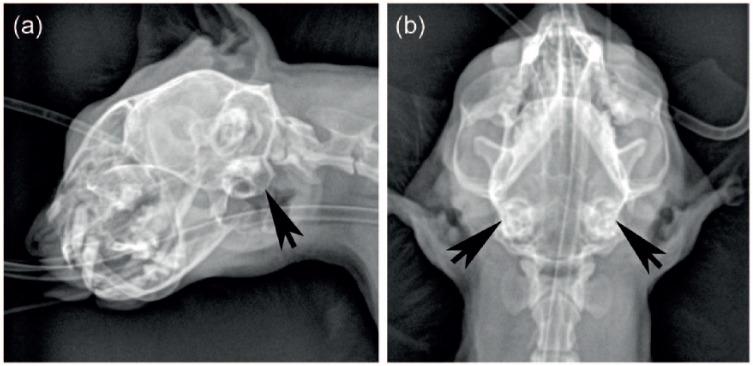

Extranodal non-B, non-T-cell lymphoma with bilateral tympanic bulla involvement in a cat.

A 9-year-old spayed female domestic shorthair cat with clinical signs suggestive of chronic recurrent otitis media and recent seizures was presented with multifocal nervous system disease, including bilateral central and/or peripheral vestibular, cerebellar and forebrain deficits. Prior to presentation, there was inadequate improvement after 6 weeks of treatment for bilateral middle ear effusion from which a highly susceptible species was cultured. This was followed by the development of seizures. Results of a complete blood count and serum chemistry were unremarkable, and a previous feline leukemia virus/feline immunodeficiency virus ELISA was negative. The cat was hospitalized overnight and had multiple seizures. The following morning the cat's mentation worsened, and the cat lost ventilatory drive after induction for anesthesia in preparation for MRI. A brain herniation event was suspected, and the cat was euthanized prior to further diagnostics. On post-mortem examination both tympanic bullae were filled with a soft, tan-colored material. Histologically, this material was composed of neoplastic lymphocytes. In addition, neoplastic lymphocytes were found in the leptomeninges, brain parenchyma, submandibular lymph nodes and pancreas. The neoplastic lymphocytes were negative for both B- and T-lymphocyte immunohistochemical markers and PCR for antigen receptor rearrangements failed to amplify target DNA, indicating non-B, non-T-cell lymphoma.

To our knowledge, this is the first report of lymphoma with confirmed bilateral tympanic bulla involvement in the human and veterinary literature. Neoplasia should be considered in cases of middle-ear effusion that do not improve adequately with appropriate antimicrobial therapy.